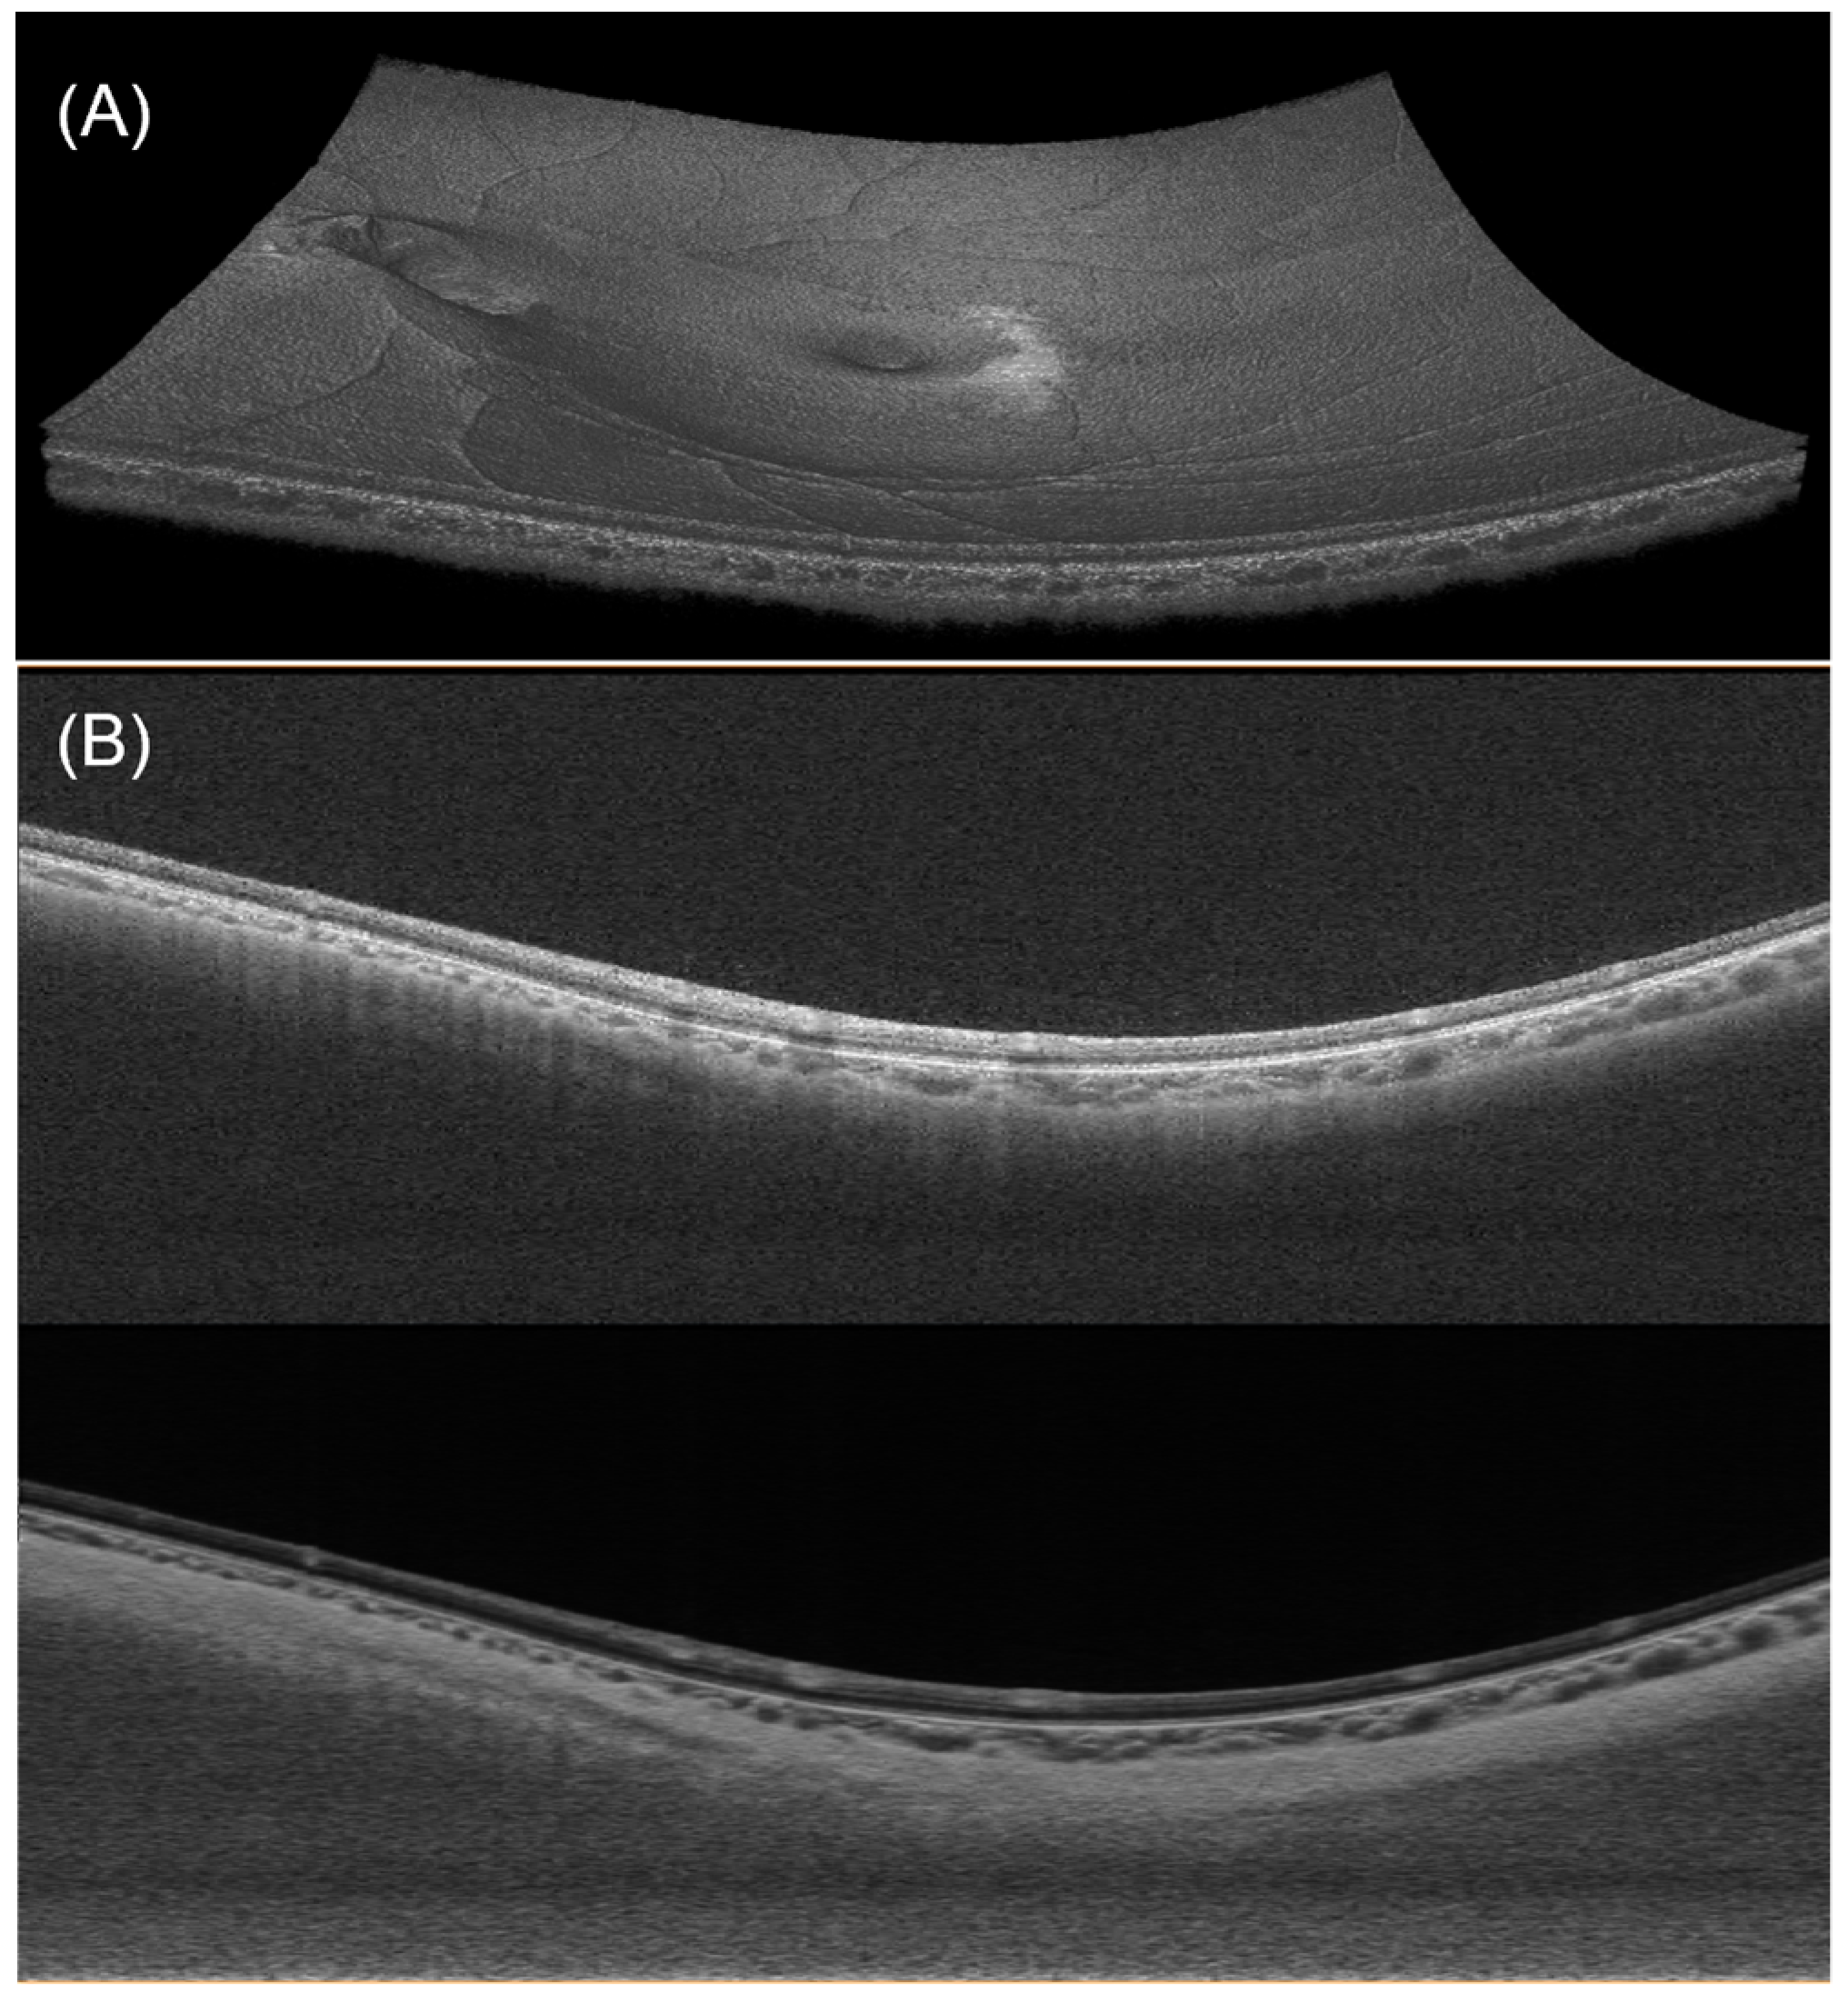

2.2. OCT Imaging and Heart Rate Measurements

2.3. OCT Image Processing and Segmentation

2.4. Measurement of Choroidal, Retinal Thickness, and Posterior Eye Curvature

3.2. Automated Segmentation Model